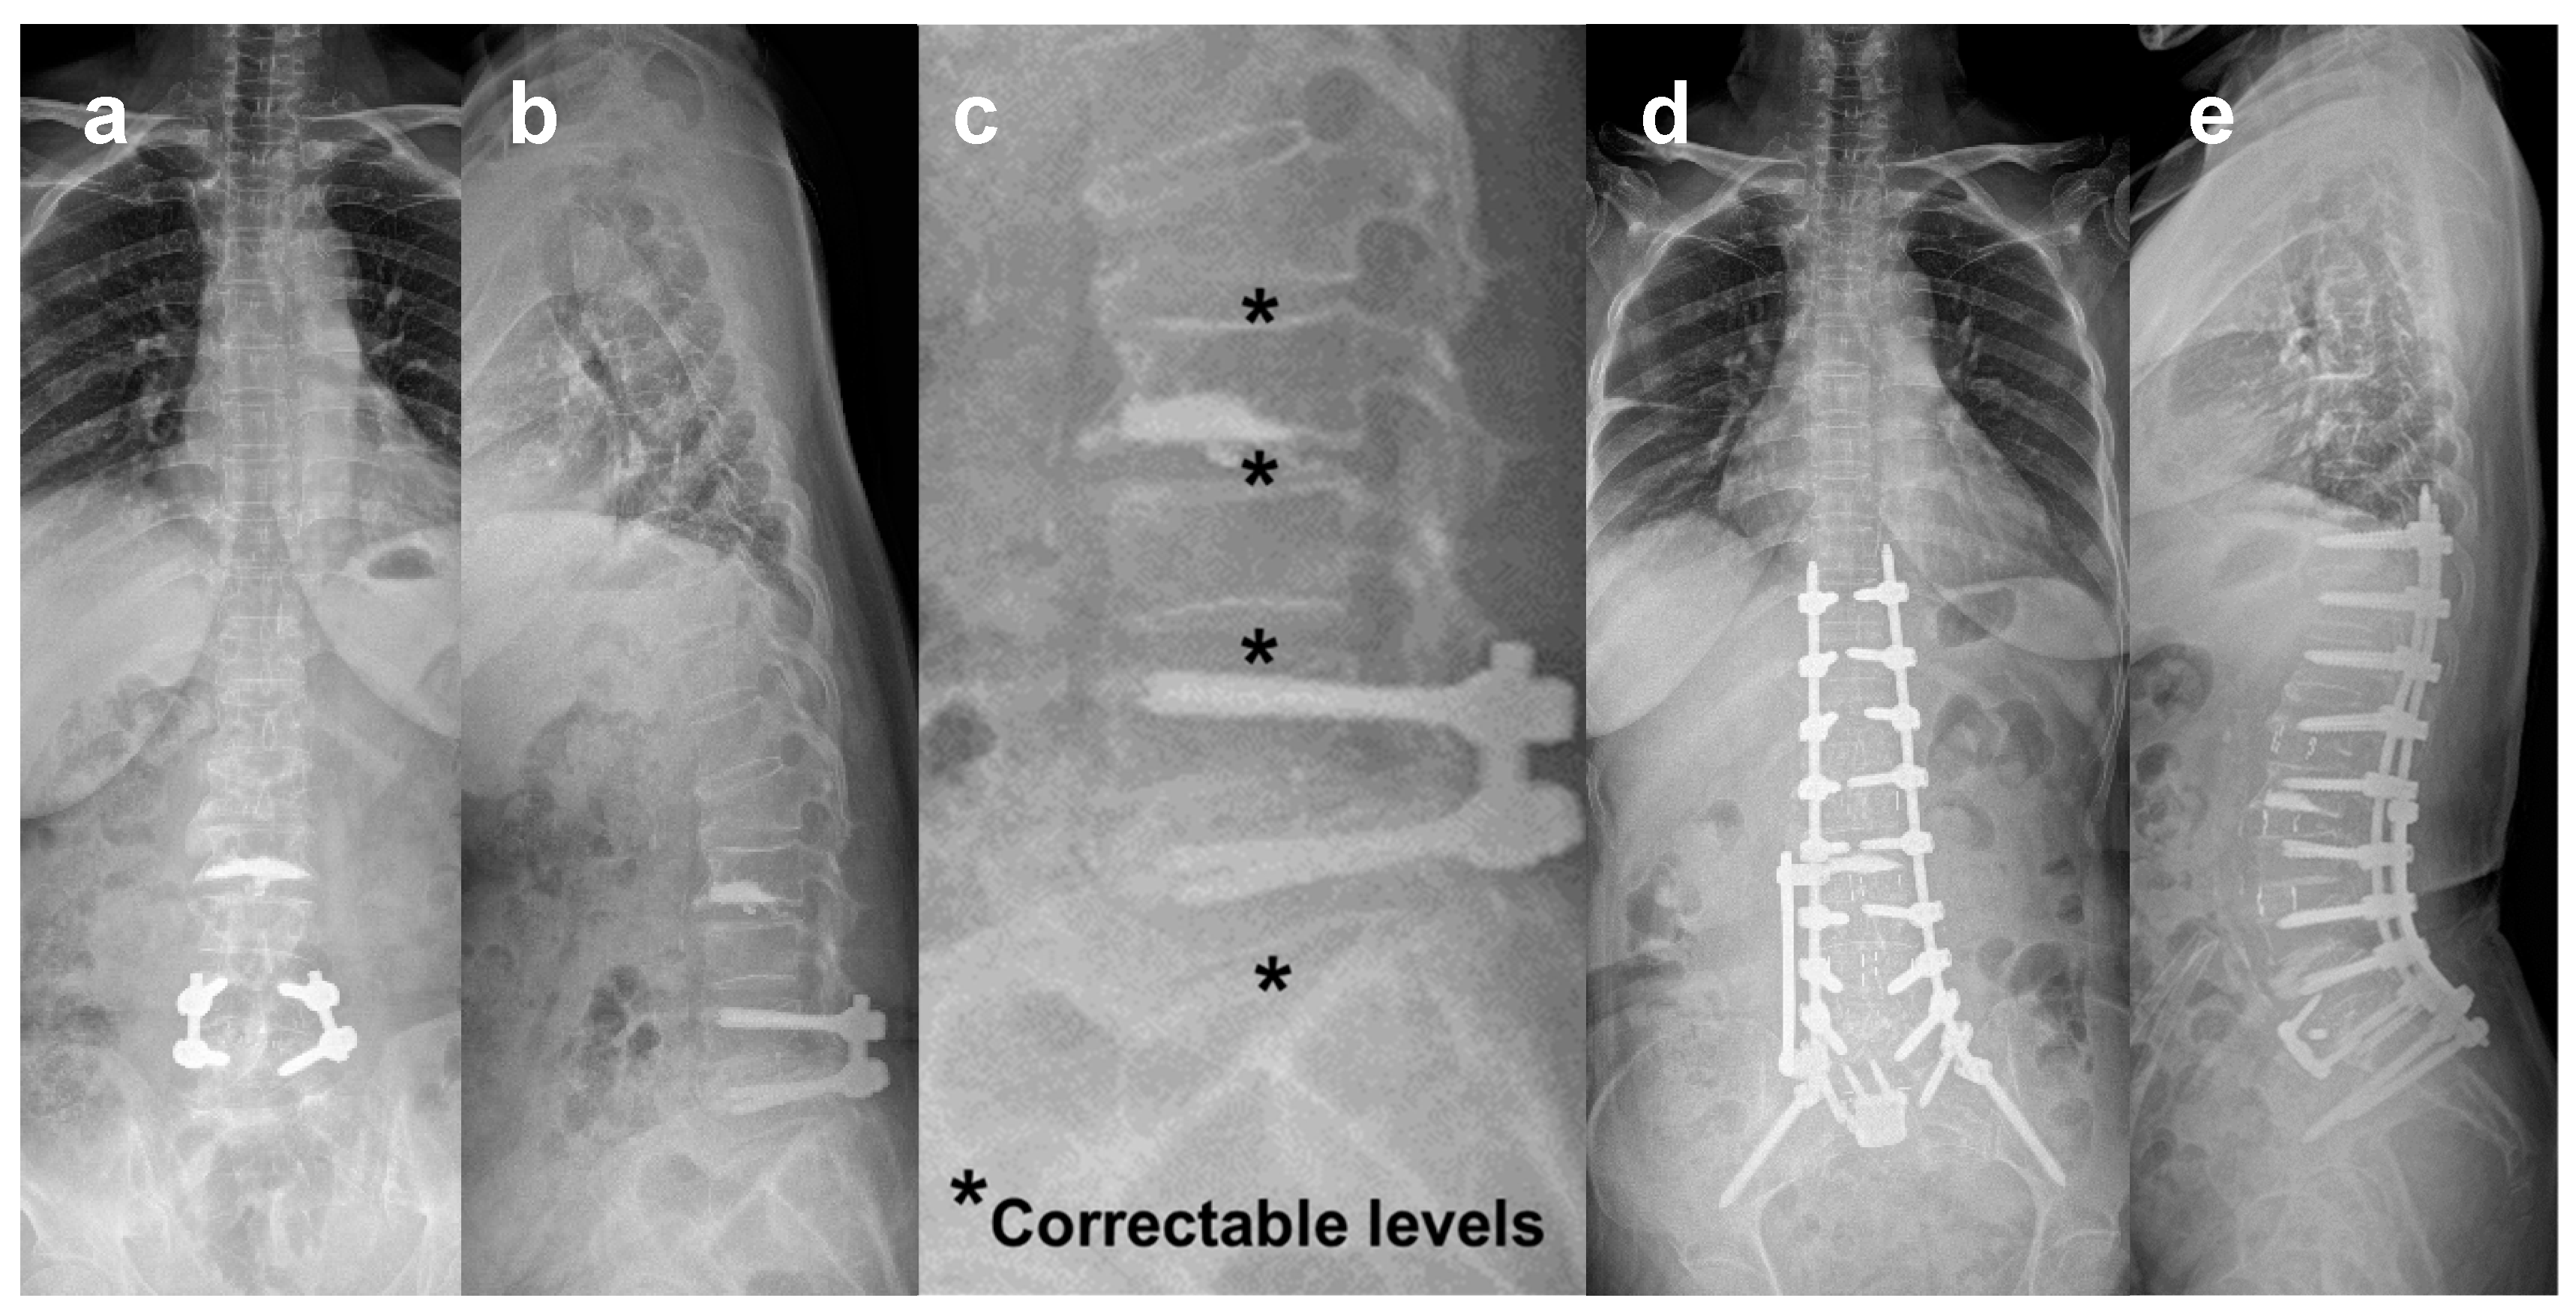

- Park, S.W.; Ko, M.J.; Kim, Y.B.; Le Huec, J.C. Correction of marked sagittal deformity with circumferential minimally invasive surgery using oblique lateral interbody fusion in adult spinal deformity. J Orthop Surg Res 2020, 15, 13–21. [Google Scholar] [CrossRef] [PubMed]